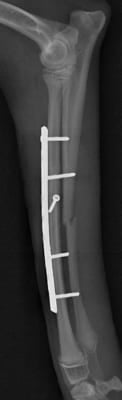

右前肢

右前肢はLag Screw固定の併用が可能だったので1期癒合

右前肢は骨片間圧迫を加えているため、骨折端同士が直接癒合します。

そのため仮骨形成が少なく、早期に癒合します。

術後19日 右前肢は治療終了です。